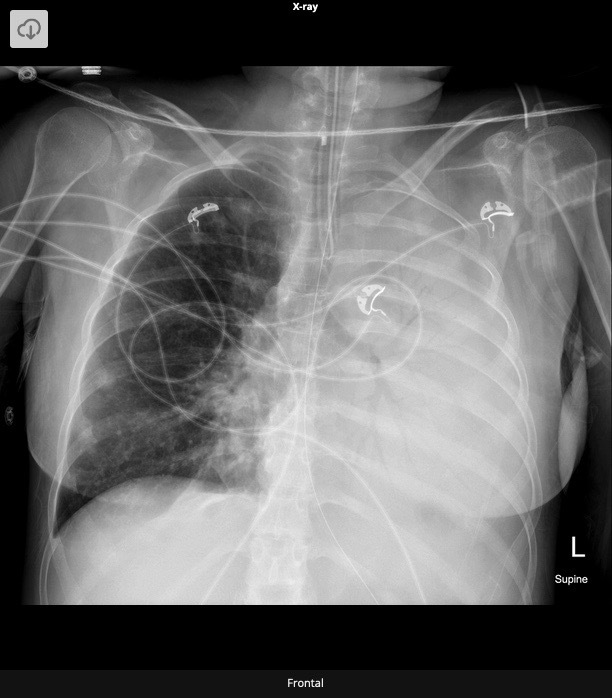

20.1 A 15-year-old boy undergoes a cardiac procedure for congenital heart disease. The intrathoracic device is a(n) (chest X-Ray shown)

c) ASD closure device

Amplatzer Device